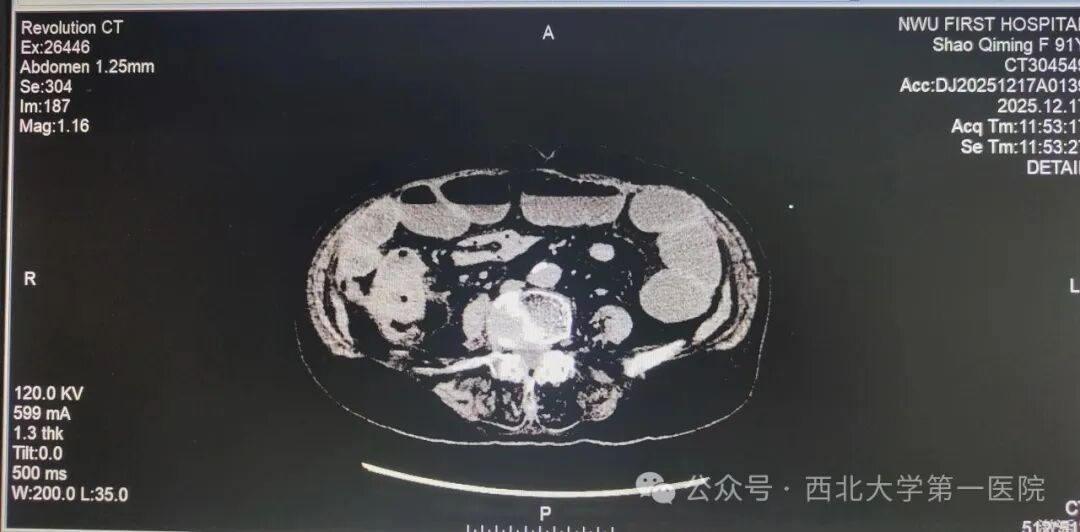

患者邵某某,因“肠梗阻、心律失常、阵发性房性心动过速”急诊入院。入院后,患者病情反复,保守治疗无效。影像学检查明确诊断为“升结肠占位病变并急性完全性梗阻”,且伴有严重的心脏扩大及代谢紊乱。面对患者91岁高龄、心肺功能差、手术风险极高的严峻挑战,医院迅速启动MDT机制。普通外科牵头,联合麻醉科、重症医学科、心内科专家进行紧急会诊,制定了“急诊手术切除病灶+全程生命支持”的精准治疗方案。

在征得家属同意后,医疗团队为患者实施了“腹腔镜辅助右半结肠切除术+回肠-横结肠侧侧吻合术”。术中,患者一度出现心律不稳及严重代谢性酸中毒,麻醉及心内科团队实时精准调控,维持了生命体征的稳定。术后,患者转入重症监护室(ICU)接受为期5天的严密监护与支持治疗,病情稳定后转回普通外科病房。经过医护人员的精心治疗与护理,患者最终康复出院。